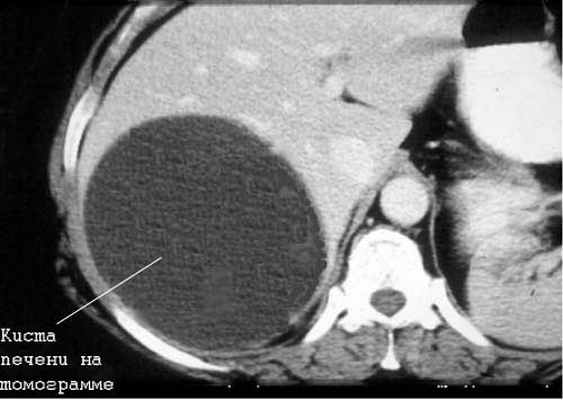

Киста печени

Чаще встречаются непаразитарные кисты. Учитывается возможность поликистозной болезни, а также солитарных и множественных истинных и ложных кист печени.

Большинство кист небольшие (диаметром 1-5 см), чаще встречаются у женщин. Значительная часть их имеет бессимптомное течение. У ряда больных отмечаются боли в правом подреберье, у одних — постоянные, у других — периодические. Существенную помощь оказывает использование УЗИ и КТ (или ЯМР), обладающие высокой разрешающей способностью. Необходимо учитывать возможность поликистоза печени.

Дифференциальная диагностика простых кист проводится также с паразитарными кистами печени (эхинококкоз). В пользу последних говорят положительные реакции с эхинококковым антигеном и Кацони, а также обнаружение в зоне опухолевидного образования обызвествлений, хотя и гемангиомы изредка могут обызвествляться.